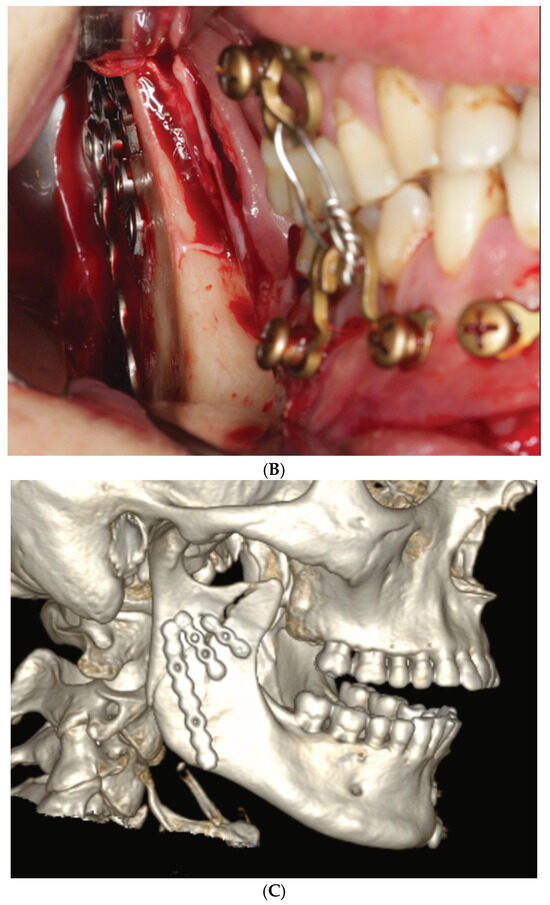

2.3. Matrix Wave System—Final Design and Technical Description

3.3. ‘In-Situ-Bending’ for Fracture Reduction